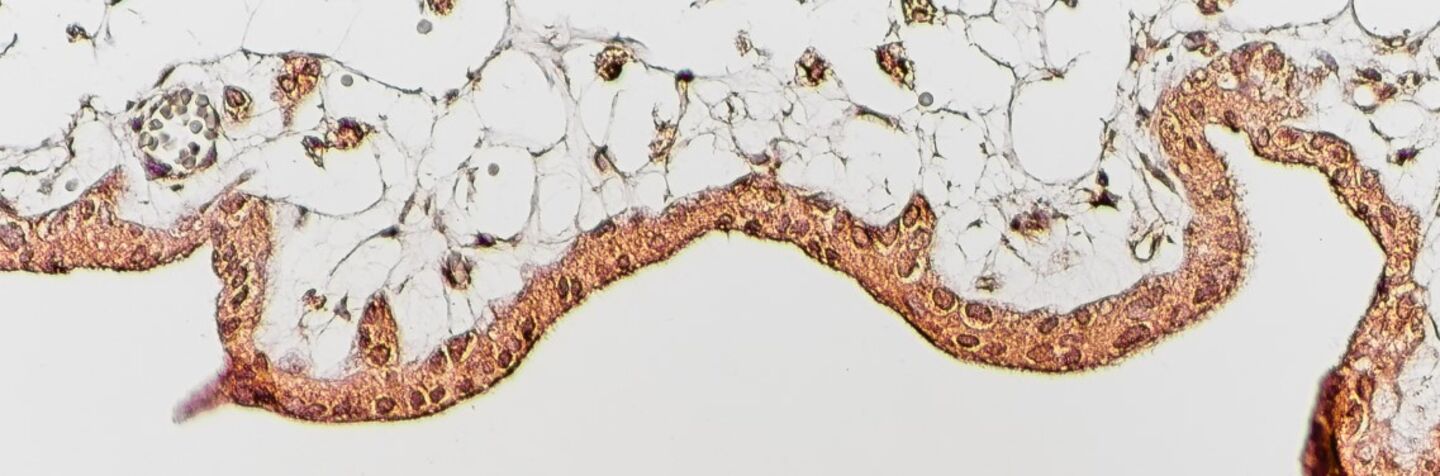

Immunhistokemi som visar celler från placentan som bildar immunreglerande molekyler, i detta fall interleukin 34 (IL-34).

Flera olika immunceller anrikas i livmodern under graviditet. Dit hör makrofager och regulatoriska T-celler, celler med specifika egenskaper som främjar immunologisk tolerans. För att moderns immunceller ska anpassas och bli toleranta behöver de få start-signaler. Vi har nyligen visat att placentan kan förmedla dessa signaler.

Det är alltså det nya och främmande organet (placentan) som själv säkerställer att moderns immunsystem växlar till tolerans. Vi undersöker nu om även andra celler i den omgivande vävnaden, stroma-celler, bidrar till immunologisk tolerans.

Interleukin-34 is present at the fetal-maternal interface and induces immunoregulatory macrophages of a decidual phenotype in vitro.

Hum Reprod, 2018:33.